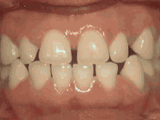

Crowding of the teeth

Patient started treatment at age eleven and wore braces for twenty-six months. He loves his new smile.